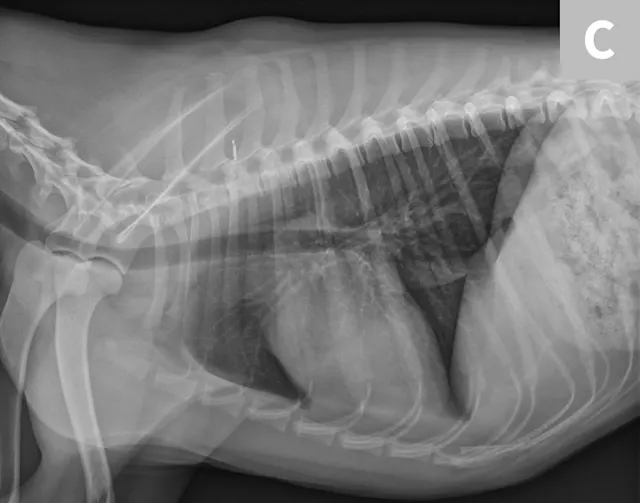

Figure 1 Ventrodorsal view obtained while holding the patient’s thoracic limbs with the hands

Images courtesy of Janet Paquette, AS, LVMT